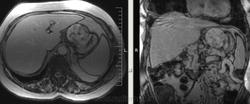

Интересные брюшные полости пошли в последнее время. Женщина, 1941 г.р. Оформлялась на операцию (по глазам), прошла УЗИ, после чего направили к нам. Жалобы только на глаза и суставы, на брюшную полость никаких. 2 года назад делала ФГС - все в порядке было. Коллеги, подскажите, пожалуйста, откуда растет эта штука? Из брюшины? Или из желудка? Или еще откуда-то?

Как-то очень близко к желудку прилежит, даже местами четко граница не прослеживается.

Может, скажу ерунду, но не от самого желудка (наружного мышечного слоя)? Ну, раз речь о панкреас и печени даже и не идет...

Согласен с Алексеем Станиславовичем. Опухоль связана со стенкой желуда, что видно на сканах 76, 77, 110, 111, стенка желудка истончена, накапливает контраст. На лейомиому в чистом виде опухоль не очень похожа, как я её себе представляю, зоны деструкции, кровоизлияния, может быть малигнизированная если. Но выглядит довольно доброкачественно в плане операбильности, имеет капсулу (не в месте контакта с желудком). Мне недавно попадалась опухоль точно такой же локализации, но имела совершенно другую структуру, прилежала к брюшине без явных признаков прорастания её. Пациентка врач, я думаю узнаю гистологию у неё, но та выглядела злокачественной.

А по УЗИ картинок нет? Расположна вне желудка ( косвенно это подтвержает факт, что её не увидели на ФГС).

лейомиома,лейомиосаркома ,гисо,шваннома